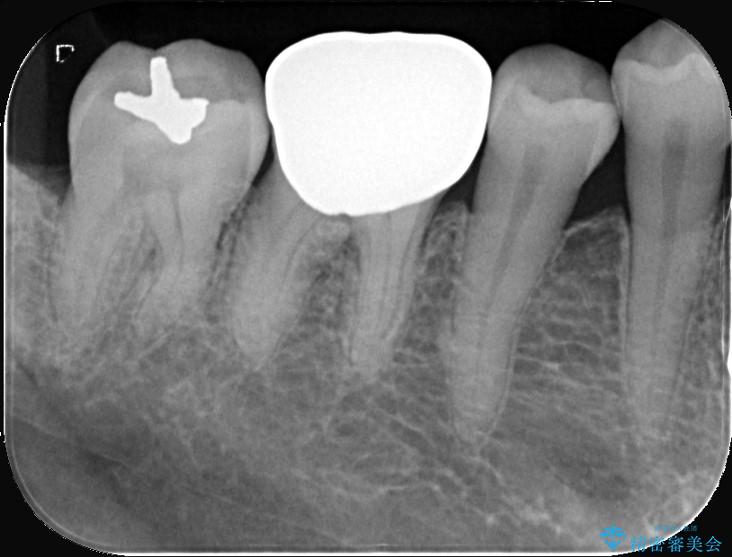

- 「銀歯を白くしたい」を主訴に来院された患者様です。銀歯を外し虫歯を除去後、オールセラミッククラウンで治療を行いました。

銀歯を外して内部の虫歯を丁寧に除去した後、オールセラミッククラウンにて修復を行いました。審美性と機能性の両面で改善が得られ、患者様にもご満足いただきました。